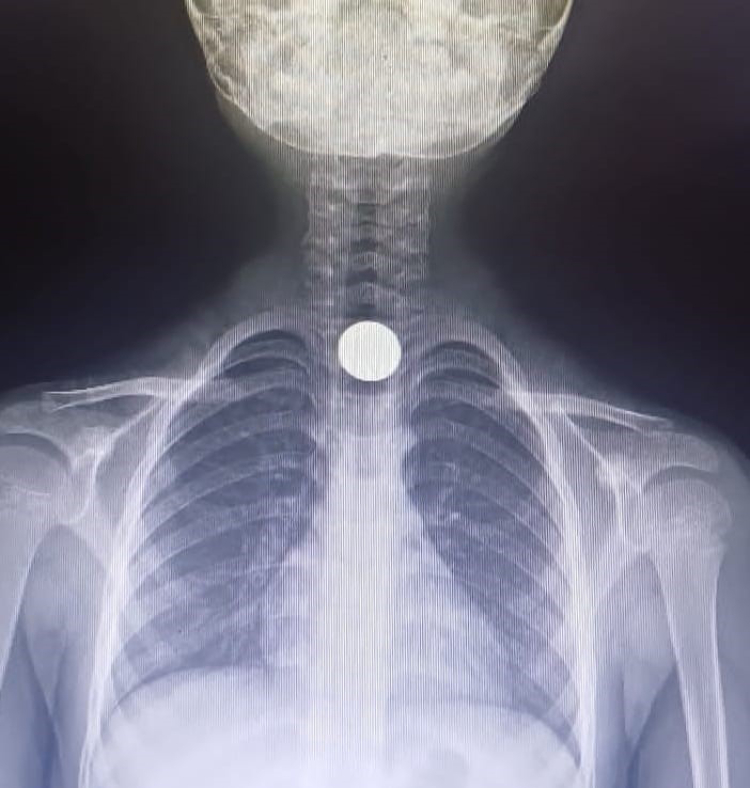

Bursa'nın İnegöl ilçesinde 5 yaşındaki çocuğun yuttuğu 50 kuruşluk madeni para yemek borusuna takıldı. Çocuk, kaldırıldığı hastanede tedavi altına alındı.

Parayı yutunca fenalaşan Yusuf durumu fark eden ailesi tarafından otomobille İnegöl Devlet Hastanesi'ne götürüldü. Hastanede doktorlar tarafından yapılan tetkiklerde paranın yemek borusuna takıldığı tespit edildi.

Çocuk, boğazındaki paranın çıkarılması için Bursa Yüksek İhtisas Eğitim ve Araştırma Hastanesi'ne sevk edildi.